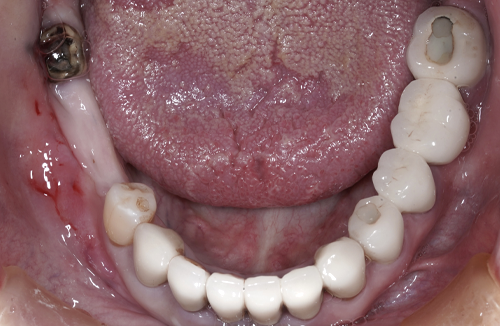

当院のインプラント治療例

― 他院で「難しい」と言われたケースにも対応 ―

※他院で骨量不足と診断された症例です。

【お悩み】

奥歯を失い、他院でインプラントの相談をしたところ「骨が足りないため難しい」と言われ、不安を感じて来院されました。

【診断】

歯科用CTにて詳しく検査を行った結果、インプラントを行うには骨量が不足している状態であることが確認されました。

【治療内容】

骨をつくる治療であるGBR(骨造成)を併用し、将来的な安定性を考慮したうえでインプラント治療を行いました。

【治療後】

現在はしっかり噛める状態となり、日常生活でも違和感なく食事を楽しんでいただいています。

【担当歯科医師からのコメント】

骨が少ないケースでも、CTによる診断と適切な治療計画によりインプラントが可能となる場合があります。

「難しいと言われた」とお悩みの方も、まずはご相談ください。